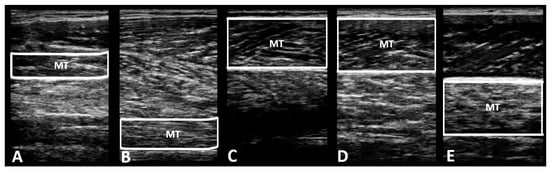

2.4.1. Portable Wireless Diagnostic Ultrasound Device

- Cheon, S.; Chang, E. Inter-rater reliability of a portable ultrasound for the quadriceps and hamstrings thickness measurement in healthy adults. Exerc. Sci. 2020, 29, 71–76. [Google Scholar] [CrossRef]

- Mickle, K.J.; Nester, C.J.; Crofts, G.; Steele, J.R. Reliability of ultrasound to measure morphology of the toe flexor muscles. J. Foot Ankle Res. 2013, 6, 12. [Google Scholar] [CrossRef] [PubMed]

- Crofts, G.; Angin, S.; Mickle, K.J.; Hill, S.; Nester, C. Reliability of ultrasound for measurement of selected foot structures. Gait Posture 2014, 39, 35–39. [Google Scholar] [CrossRef]